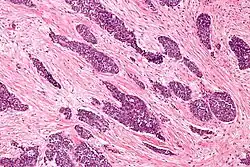

Characteristics of desmoplastic stromal response

A desmoplastic response is characterized by larger stromal cells with increased extracellular fibers and immunohistochemically by transformation of fibroblastic-type cells to a myofibroblastic phenotype.[2] Myofibroblastic cells in tumors are differentiated from fibroblasts for their positive staining of smooth-muscle actin (SMA).[2] Furthermore, an increase in total fibrillar collagens, fibronectins, proteoglycans, and tenascin C are distinctive of the desmoplastic stromal response in several forms of cancer.[14] Expression of tenascin C by breast cancer cells has been demonstrated to allow for metastasis to the lungs and cause the expression of tenascin C by the surrounding tumor stromal cells.[15] In addition, tenascin C is found extensively in pancreatic tumor desmoplasia as well.[16]